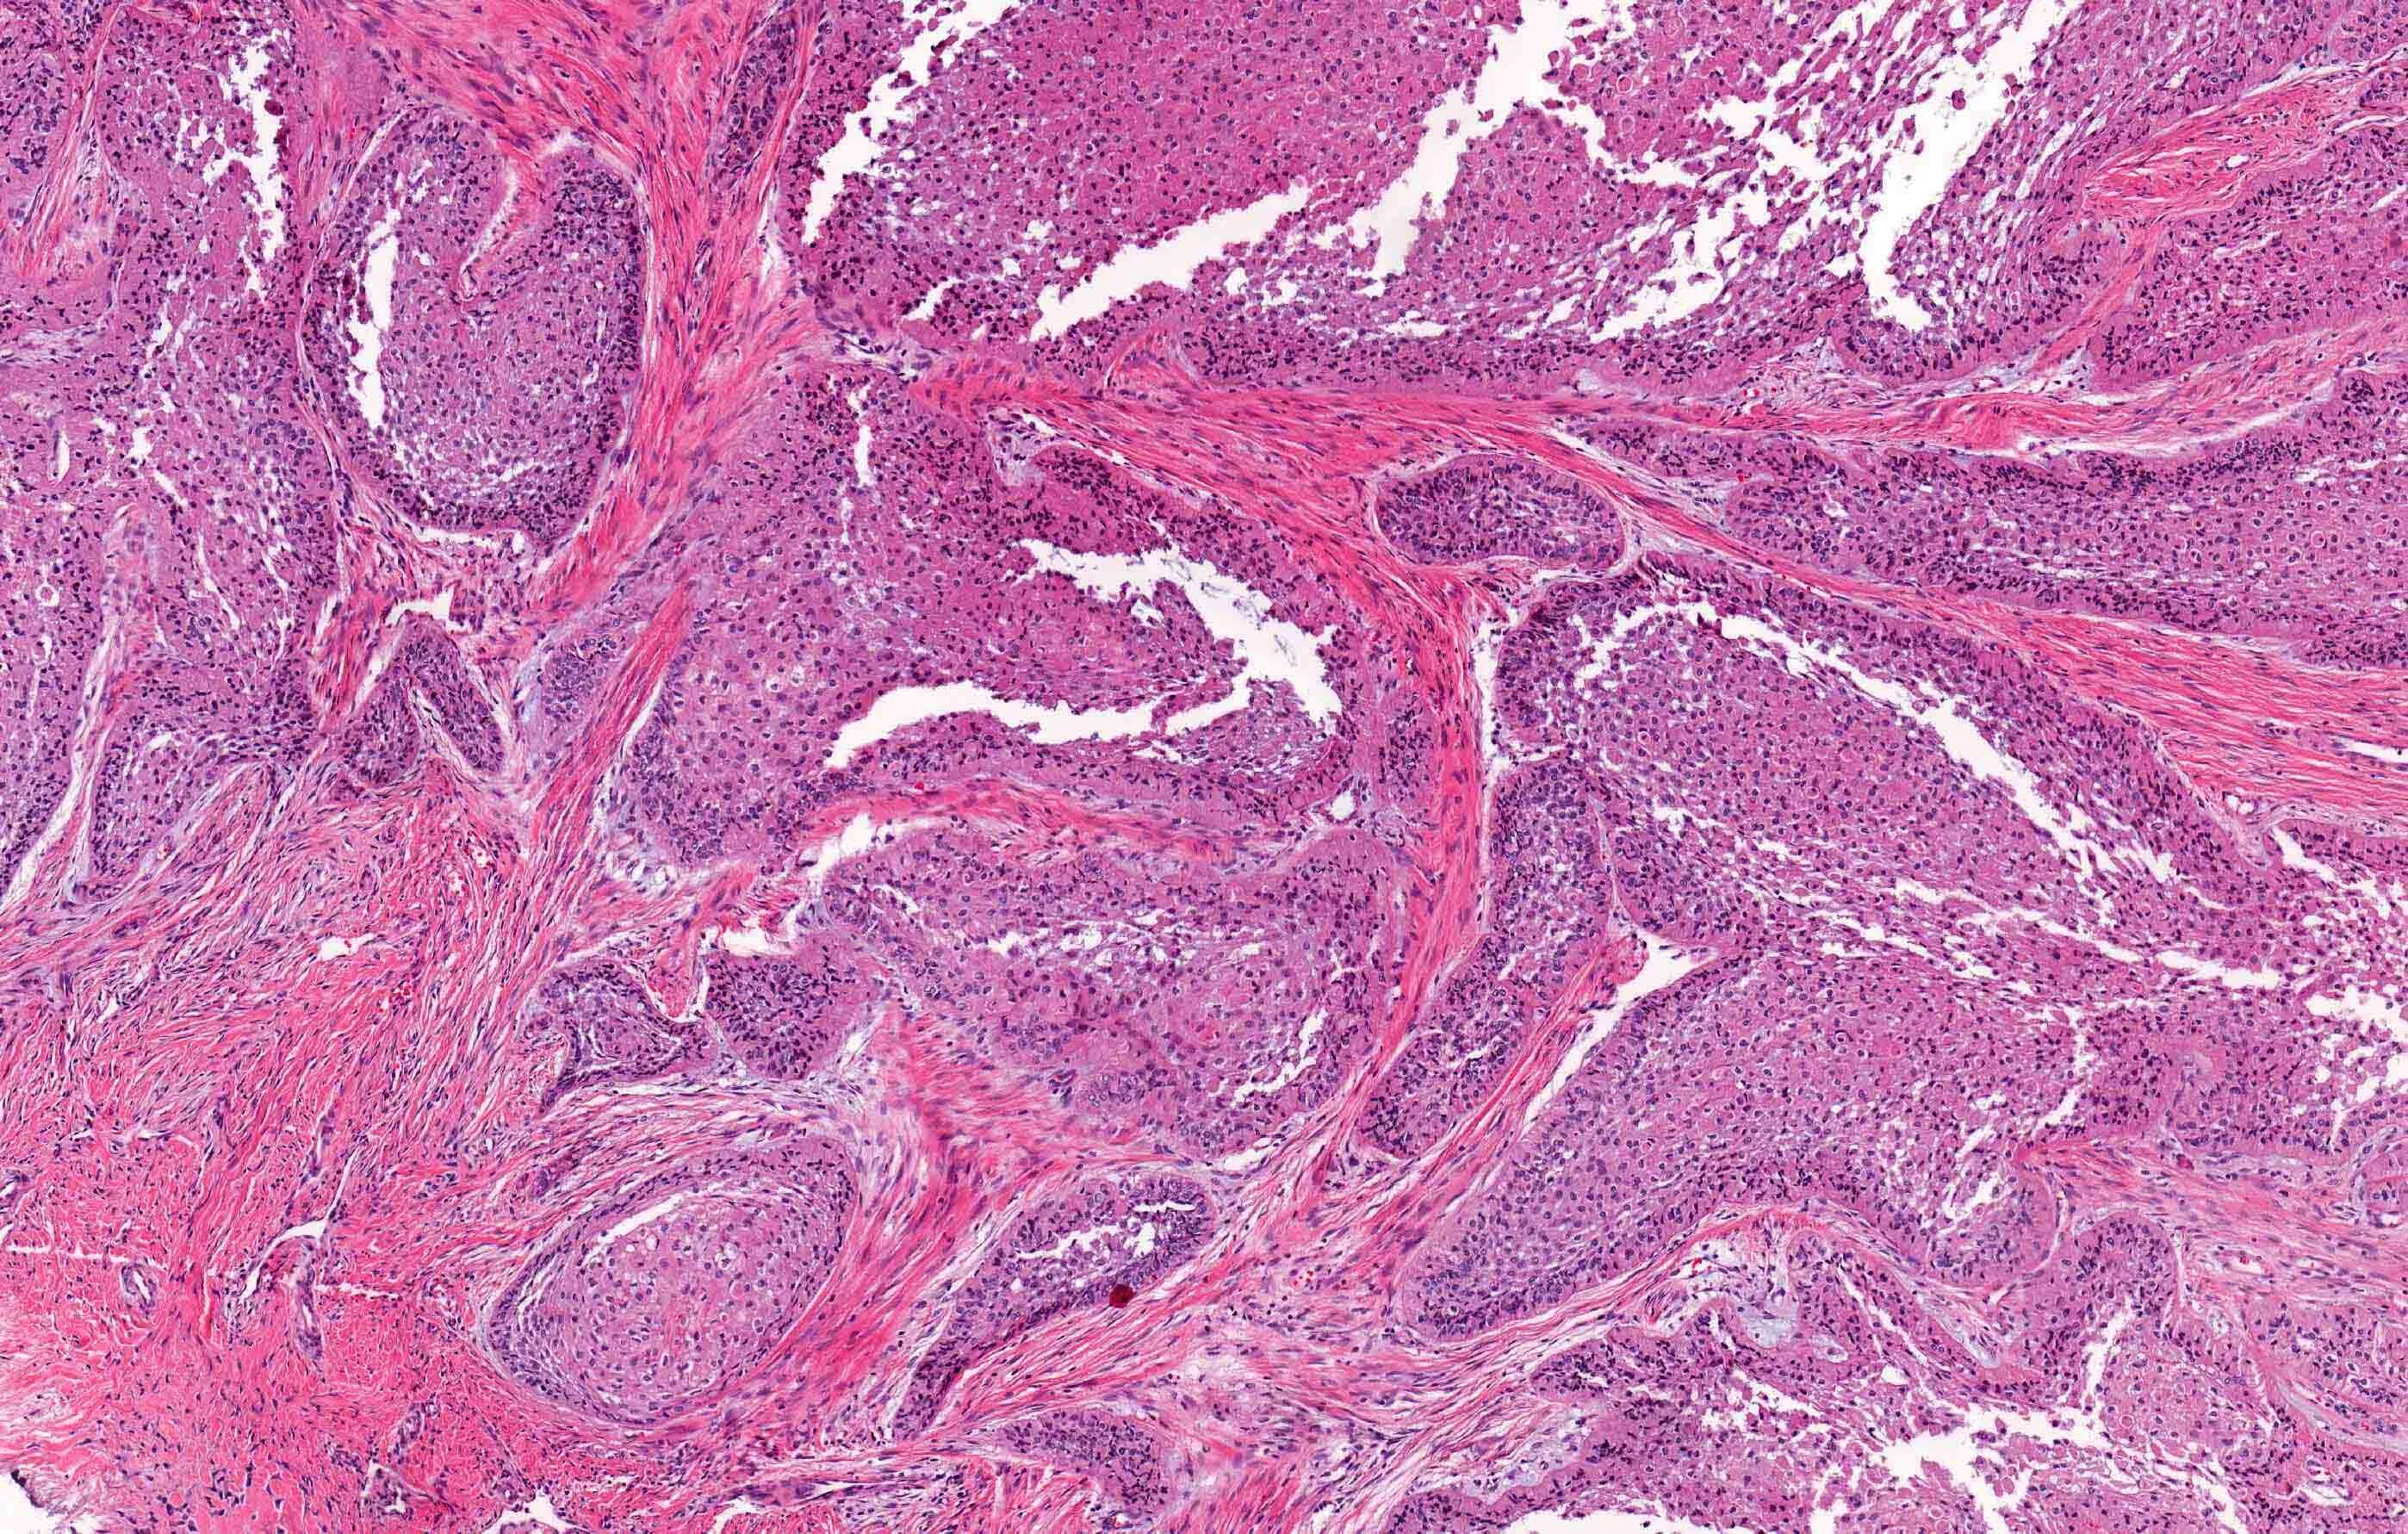

Гистология челюстей